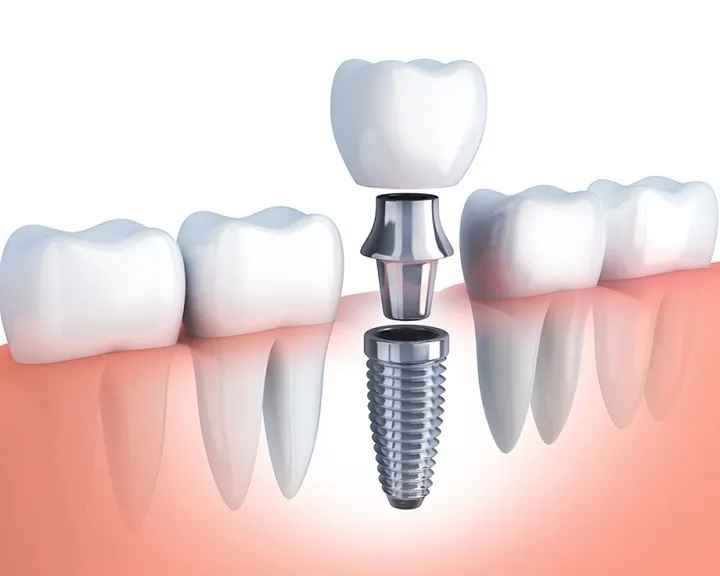

Tình trạng mô răng còn lại

Khi bọc sứ toàn hàm, một phần răng thật sẽ bị mài mòn. Nếu phần cùi răng còn lại sau khi mài vẫn đủ, khả năng niềng răng của bạn sẽ cao hơn. Khi niềng răng, lực sẽ được truyền qua lớp mão sứ để di chuyển răng. Tuy nhiên, hiệu quả của việc di chuyển răng sẽ bị giới hạn so với răng thật. Một số lúc sẽ có nguy cơ răng sứ bị bật ra khi áp dụng lực niềng. Vì vậy, tình trạng mô răng thật còn lại sau khi bọc sứ là yếu tố quan trọng quyết định việc niềng răng.

Chất lượng của răng sứ

Một yếu tố khác là độ chính xác và chất lượng của răng sứ. Một số mão sứ không được gắn chặt, không kín khít. Vì thế nguy cơ bị bật ra khi chịu lực kéo từ khí cụ niềng rất cao. Để đánh giá mức độ kín khít của mão sứ, nha sĩ sẽ sử dụng dụng cụ thăm khám. Từ đó kiểm tra vùng chân răng sứ. Nếu phát hiện có khe hở hoặc vùng răng sâu, bác sĩ sẽ yêu cầu làm lại răng sứ. Công việc này sẽ được thực hiện trước khi tiến hành niềng để đảm bảo an toàn.